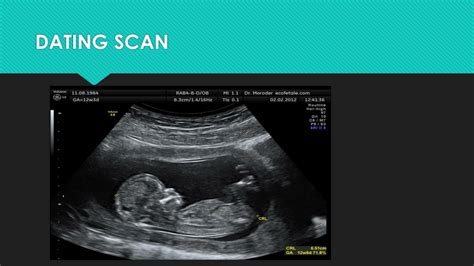

When is a dating scan done

This is offered as a blood test between 14 and 20 weeks of pregnancy. This test is called the quadruple test and is not quite as accurate as the combined test.